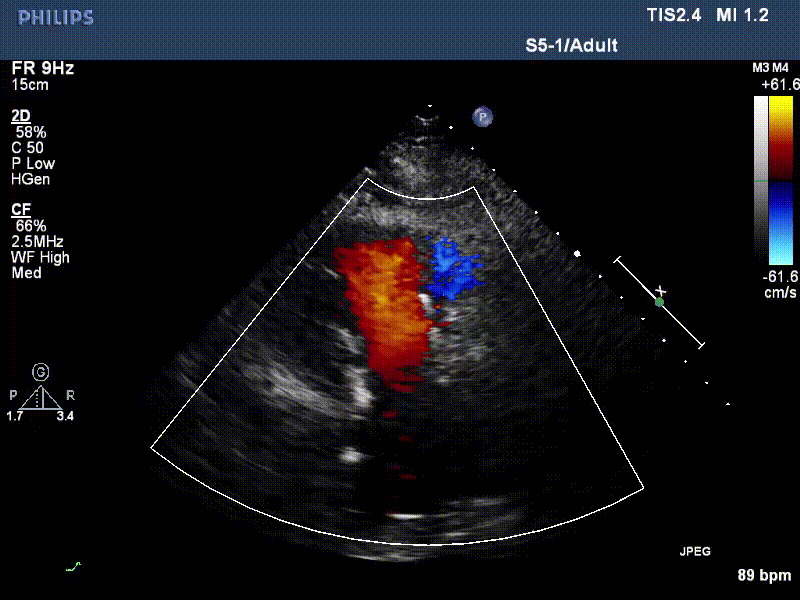

流并分別伴有房顫和房撲,高外科手術風險。術前超聲提示,兩例患者下腔靜脈寬度分別為13mm和29mm,右房內(nèi)徑(上下徑和左右徑)分別為52×41mm和53×43mm,彩色多普勒顯示極重度三尖瓣反流,VCW分別為14×15mm和10mm。

1年前,兩例患者因難治性雙下肢水腫輾轉(zhuǎn)多家醫(yī)院尋求救治,考慮到兩例患者高齡、基礎疾病多、STS評分高,不適合傳統(tǒng)外科開胸手術,葛均波院士及其團隊周達新教授、潘文志教授、張源博士、陳莎莎博士、陳丹丹博士聯(lián)合心外科王春生、魏來主任,麻醉科繆長虹、郭克芳主任以及心超室的潘翠珍教授、李偉教授共同討論決定,采用我國創(chuàng)新器械LuX-Valve Plus經(jīng)血管三尖瓣置換系統(tǒng)為患者進行手術。相較于第一代產(chǎn)品LuX-Valve,LuX-Valve Plus經(jīng)血管三尖瓣置換系統(tǒng)對輸送系統(tǒng)進行了全面升級,實現(xiàn)了經(jīng)頸靜脈入路的方式,進一步減小了手術風險和對患者的創(chuàng)傷。目前隨訪1年心超結(jié)果顯示,三尖瓣極重度反流消失,人工三尖瓣瓣膜穩(wěn)定牢固,瓣葉活動度良好,右心室及下腔靜脈明顯縮小,心輸出量增加。兩位老人手術后沒有出現(xiàn)過胸悶氣促的癥狀,下肢水腫緩解,活動耐力提升,生活質(zhì)量也大為提高。

圖2 患者植入LuX-Valve Plus后,1年隨訪心超提示無三尖瓣反流